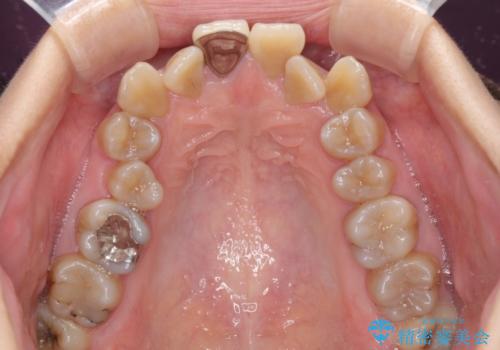

- 八重歯や前歯のデコボコを気にして来院された患者様です。

歯列が前方に傾斜しており、デコボコが強かったため、上下左右第一小臼歯4歯を抜去し、ワイヤー装置による矯正治療を行うこととしました。

上下の正中がずれていましたが、抜歯矯正であったので、極力正中位置を合わせるように治療を進めて行きました。